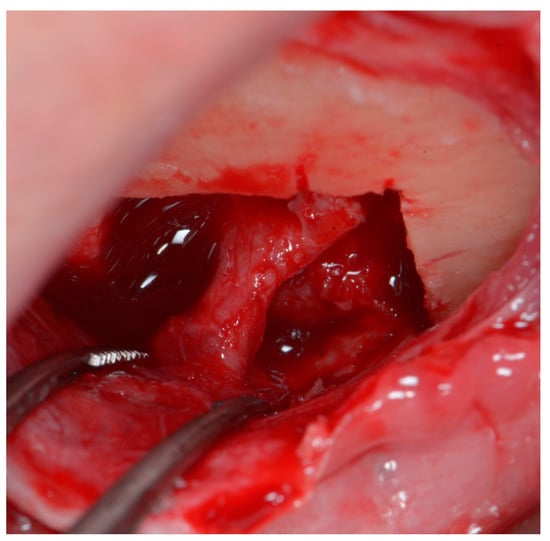

The second part of osteotomy creates diagonal lines from the corners of the rectangular area to the foramen, with special care not to damage the neurovascular bundle. Although piezosurgical tips are considered to cause very little damage to soft tissues, when used with excessive force, they may still result in irreversible injury [19]. The diagonal cuts enable the sectioning of the rectangular piece of the bone ring into four smaller separate pieces. If they are mobile, they can be easily removed. In case they are still fixed, due to the trabeculae of the cancellous bone, the pieces should be gently luxated with a rigid root elevator (or another rigid surgical tool). Using elastic tools deprives the operator of feeling how the bone behaves under applied force; hence it could potentially jeopardize the procedure, and it is therefore not recommended. When all bone pieces are mobile, they should be gently removed one by one, leaving the mental nerve loose (Figure 4).

The operator may see that the bundle is indeed loose, as it straightens under gentle manipulation and pulling the flap (Figure 5), confirming the releasing effect of the procedure.

Figure 4. Mental foramen after enlargement and decompression of the nerve. The bundle is left loose; therefore, it has a curved shape.